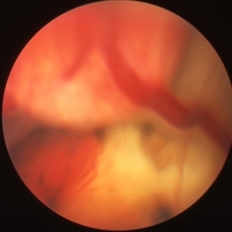

Large retinal angioma OS secondary to Von Hippel-Lindau.

Condition/keywords: retinal angioma, Von Hippel-Lindau